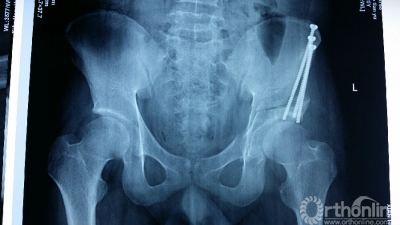

小赵今年20岁,因为髋臼发育不良并骨关节炎辗转多家省内外的大医院求诊,但专家们的回答却接近一致:要么现在做关节置换,要么“将就”到难以忍受的时候再做关节置换。人工关节置换可暂时获得疼痛缓解和行走功能,但随着时间的推移,不可避免的二次甚至三次翻修手术让20岁的小赵怎么也乐观不起来。抱着最后一线希望他慕名来到姚建锋副院长的门诊求治,姚院长和马建兵主任组织关节外科膝关节病区全科医生经过反复讨论,决定为小赵实施难度极大但疗效最好的髋臼周围截骨术(即Ganz截骨术),尽可能长久地保住属于他自己的髋关节。

Ganz截骨术是1983年由瑞士伯尔尼医院的Ganz医生开创的髋臼周围截骨术,因为难度高,风险大,被形容为骨科手术领域的“珠穆朗玛峰”。用通俗的话来说,正常髋关节的髋臼就像一顶帽子,股骨头就像脑袋,发育不良的髋臼就像帽子歪戴着,在不知不觉中将髋关节磨坏。Ganz截骨术就是把戴歪了的帽子正过来,改变了髋臼覆盖的方向,增加了髋关节对股骨头的覆盖面积,使得年轻的髋臼发育不良的患者大大延缓甚至免于人工关节置换。但迄今为止国内只有少数几家医院开展这项手术,在西北五省更是鲜有报道,而这也将是西安市红会医院开展的第一例。

术前,专家们利用数字骨科实验室中3D打印技术打印出1:1的骨盆模型,并在骨盆模型上完成预截骨。在姚建锋副院长耐心细致的的指导下,得益于充分细致的术前计划,马建兵主任的手术小组在短短两小时之内便顺利完成了Ganz截骨术,术中失血量也大大低于预期。现在患者已安全度过围手术期,正在积极康复训练,预计2-3个月之后,患者便可行走自如。